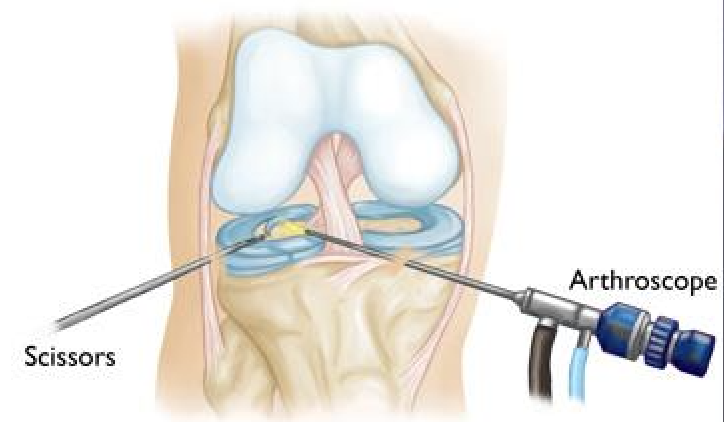

If knee pain, swelling, locking, or instability is affecting your daily activities, private knee arthroscopy...